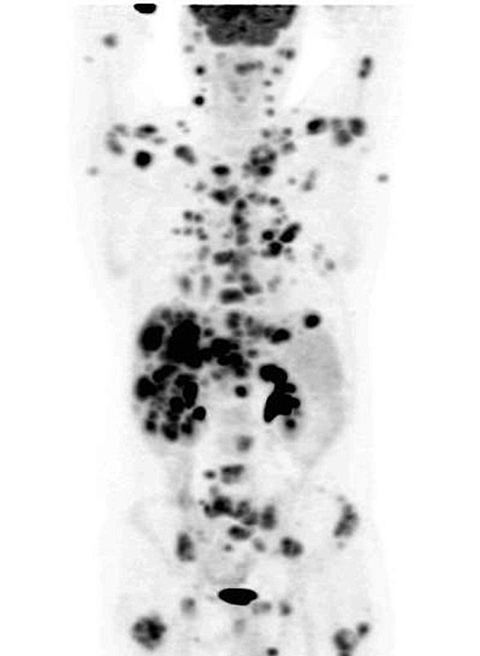

Các bác sĩ cho biết, trong cơ thể Ian Brooks có tới hơn 70 khối u nguy hiểm và họ đã dùng tất cả các phương pháp điều trị nhưng đều vô hiệu.

Kết quả chụp X-quang lần thứ hai sau 12 tuần điều trị cho thấy hơn 70 khối u ác tính trong khắp cơ thể ông đã hoàn toàn biến mất.

Ngoài ra, vết đậm trong thận và bàng quang của ông chứng tỏ chúng cũng hoạt động hoàn toàn bình thường. Sau vài ngày theo dõi tại bệnh viện, sức khỏe của Ian đã hoàn toàn bình phục để có thể xuất viện.